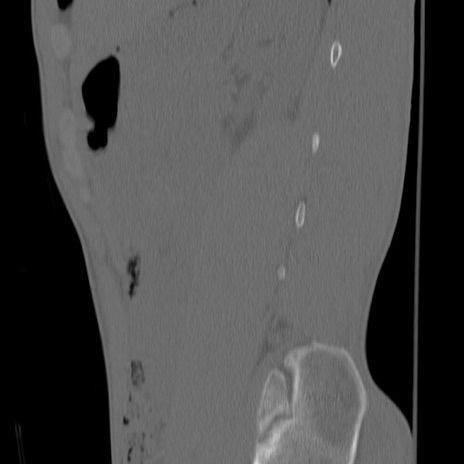

症例3 腰椎CT(矢状断像)

【症例】30歳代男性

【主訴】腰痛

【現病歴】本日旅行先で観光中に、友人と衝突し転倒し受傷。

【身体所見】麻痺なし、右下腿内側前面外側、左下腿内側に知覚鈍麻・しびれ

腰椎CT

冠状断像